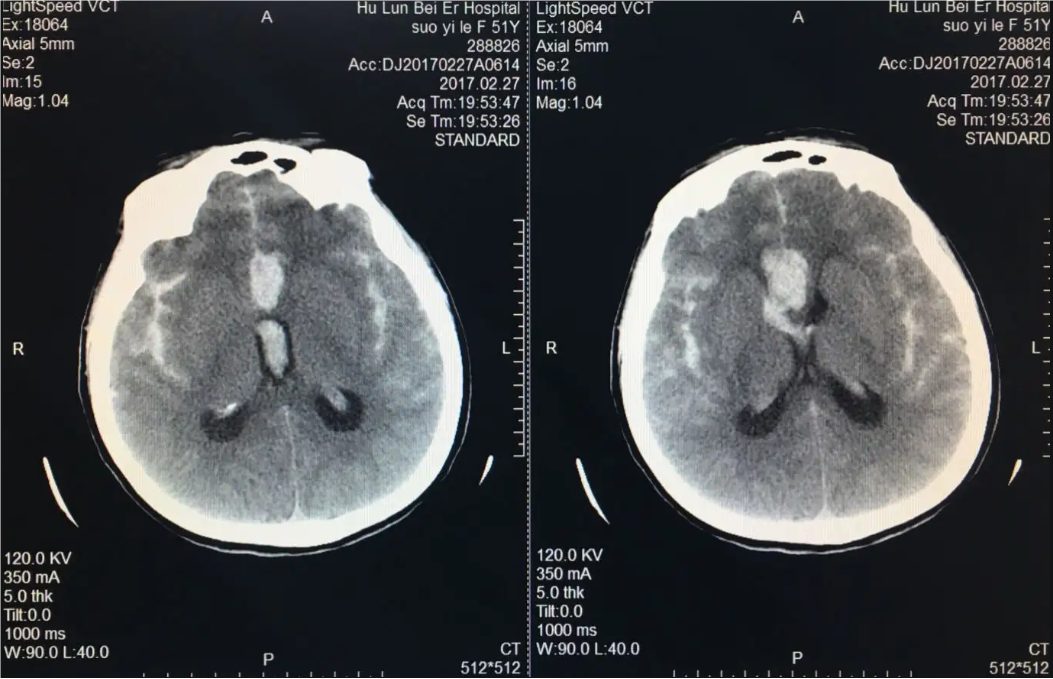

1. 頭部CT掃描:可以快速評(píng)估腦出血和動(dòng)脈瘤的存在。